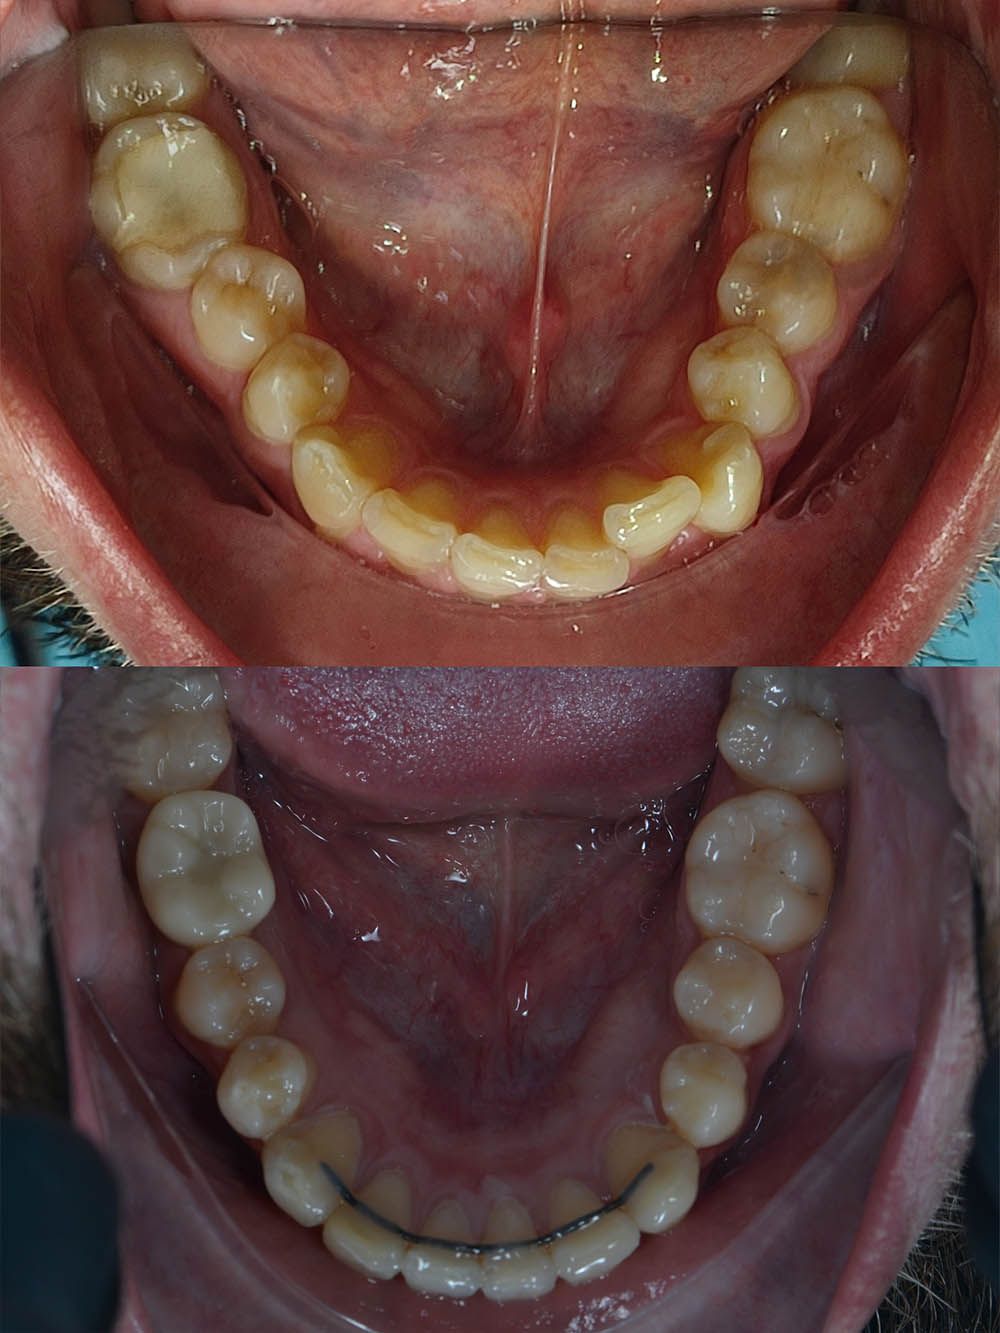

15 месяцев лечения на брекет-системе

15 месяцев лечения на брекет-системе

15 месяцев лечения на брекет-системе

15 месяцев лечения на брекет-системе

15 месяцев лечения на брекет-системе

15 месяцев лечения на брекет-системе